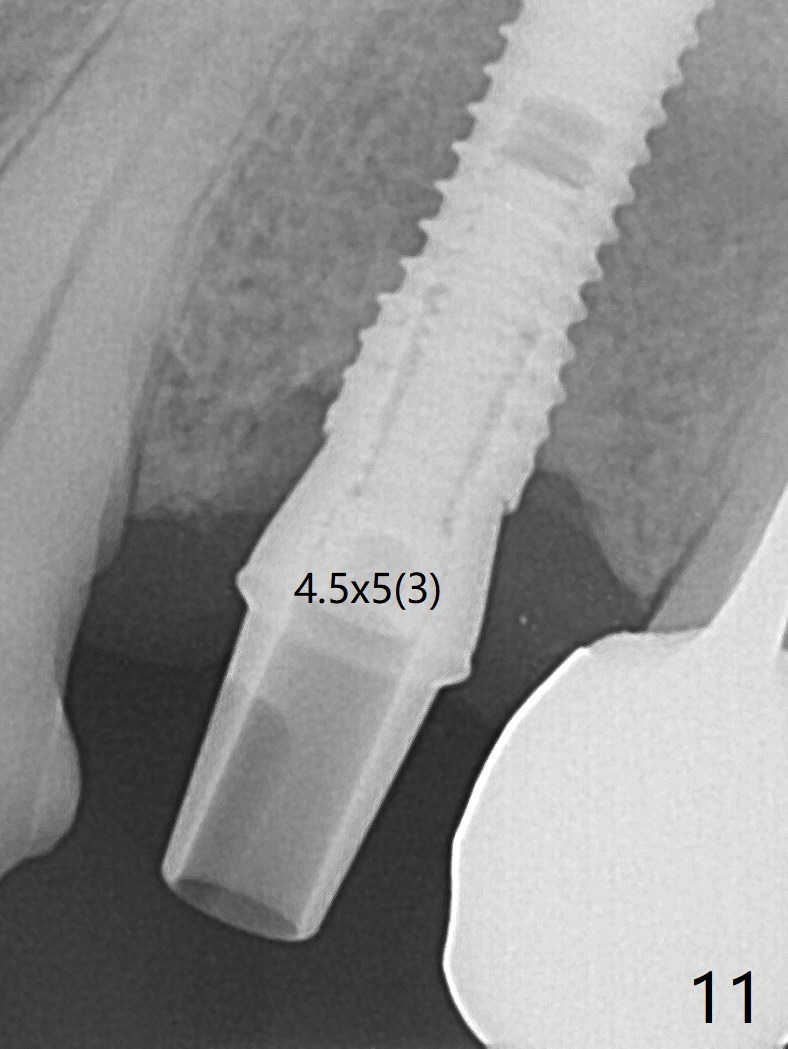

After extraction of the oval-shaped residual roots at #12 (Fig.1), osteotomy is initiated in the palatal socket for 18 mm; since the root of the canine curves distal (Fig.2 red dashed line), the osteotomy cannot afford to move mesial and extend more apical.  A 3.8x15 mm implant is placed with > 50 Ncm (Fig.3).  With immediate placement of a 4.5x4(3) mm abutment, an immediate provisional is fabricated to close the sockets (Fig.4 P).  The provisional has clearance from the RPD clasps (Fig.5).  In fact the implant could be longer, as shown by immediately postop panoramic X-ray (Fig.6).  The implant seems to be osteointegrated 3 months postop (Fig.7).  The tooth #13 is symptomatic with caries (Fig.8 C) 7 months post #12 crown cementation; the #13-15 FPD dislodges.  The upper left quadrant is cold and hot sensitive 2.5 months post RCT (Fig.9); although there is mild percussion at #13, pulpal test shows that the tooth #15 has lingering pain.  The FPD was recemented temporarily after RCT; it cannot be removed.  The implant crown has been loose for several months during the pandemic before he returns 2 years 7 months post cementation.  In fact the abutment has been not seated completely (from Fig.3 to 9).  The crown/abutment is removed from the mouth; the crown is sectioned and separated from the abutment; the latter is reseated, but incompletely (Fig.10 <).  With suspicion of the mesial crestal contact, profile drills 4.6 and 5.5 mm are used without effect.  A new (old probably being worn) and longer (easy to turn in the narrow space) abutment is finally seated completely (Fig.11 (no gap)).  After occlusal adjustment, abutment level impression is taken for a new crown.